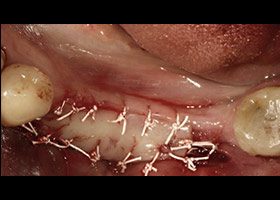

proimages/case/Artificial_implant/Horny2.jpg

移植角質化牙齦